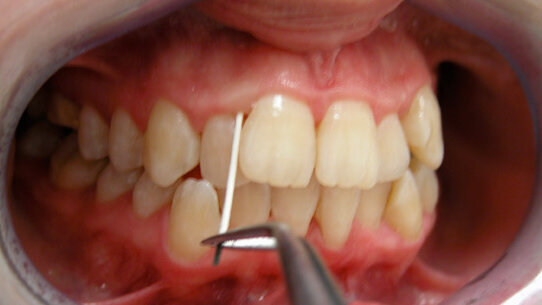

La saliva è uno dei liquidi corporei, ma diversamente da altri (sangue, liquido cefalo rachidiano) può essere raccolto in modo non invasivo e questo facilita la collaborazione del paziente. È il liquido a cui gli operatori del settore hanno accesso “obbligato” e permette non solo di fare diagnosi per la patologia odontostomatologica (per esempio malattia parodontale) ma anche per altri distretti corporei o patologie sistemiche. Sotto questo profilo l’operato dell’odontoiatra/igienista può essere visto come servizio al pari di un medico di medicina generale che poi, ricevuto il referto, indirizza il paziente allo specialista.

Esempi di applicazione specifica in odontoiatria sono la verifica della tipologia e carica batterica in parodontologia, implantologia, ortodonzia e protesi nonché il profilo di rischio genetico nei pazienti con familiarità positiva per patologia parodontale. In prevenzione primaria stanno emergendo indicazioni anche in campo oncologico.

Prevenzione, innanzitutto. È su questo principio che si fonda l’impiego del “test salivare”, che può essere introdotto nella pratica quotidiana per ...